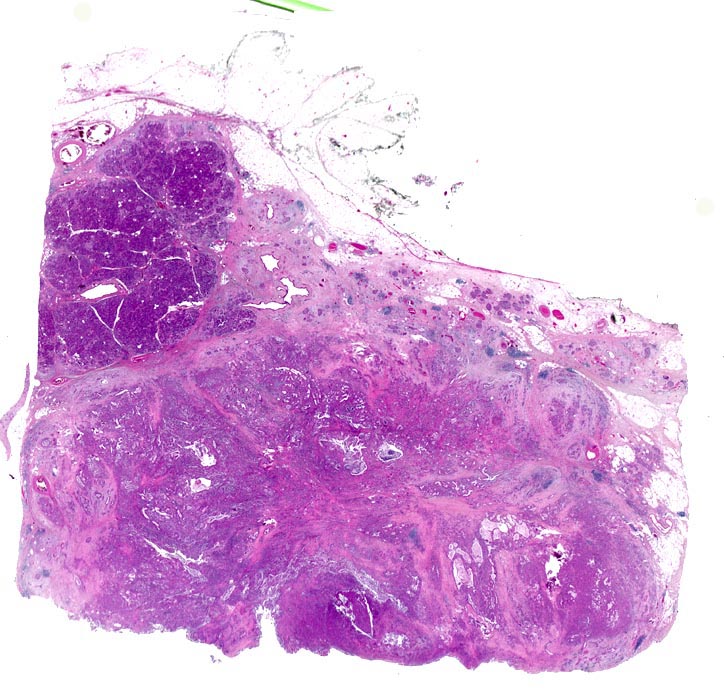

Die meisten Pankreaskarzinome sind mässig bis hoch differenziert und führen zu einer deutlichen desmoplastischen Stromareaktion (derbe Konsistenz). Hochdifferenzierte Tumoren (> 1502) können sehr ähnlich aussehen wie eine chronische Pankreatitis (> 4243). Im Gegensatz zur Pankreatitis sind die neoplastischen Drüsen verformt oder rupturiert und zeigen zelluläre Atypien (grosse polymorphe Kerne mit prominenten Nucleolen). Die Tumordrüsen sind unregelmässig im Stroma angeordnet und nicht lobulär wie in der Pankreatitis. Nicht selten ist eine Nervenscheideninvasion nachweisbar (> 5884). Gelegentlich zeigen die Gänge im tumorfreien Parenchym dysplastische Veränderungen oder der Tumor breitet sich intraduktal entlang des Pankreasganges aus.

• Unregelmässige Anordnung der Drüsen (keine Läppchenarchitektur erkennbar).

• Desmoplastisches Stroma.

• Rechts oben Reste von nicht neoplastischem Pankreasparenchym mit fokaler chronisch obstruktiver Pankreatitis als Folge von tumorbedingten Gangobstruktionen: Vollständige Atrophie des exokrinen Pankreas bei erhaltenen Inseln. Ersatz des atrophen Parenchyms durch Fibrose. Chronisches Entzündungsinfiltrat.